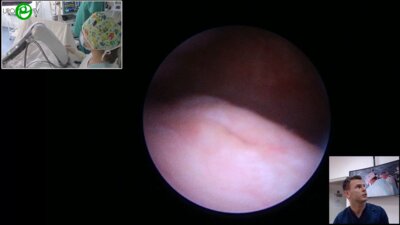

Лабиринты детской урологии. Микрохирургическая варикоцелэктомия подпаховым доступом у детей и подростков